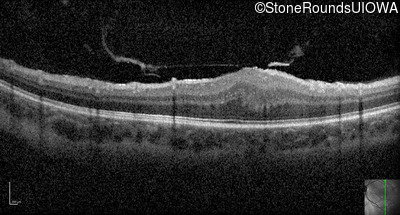

Optical Coherence Tomography - Right - 20/400

Exemplar